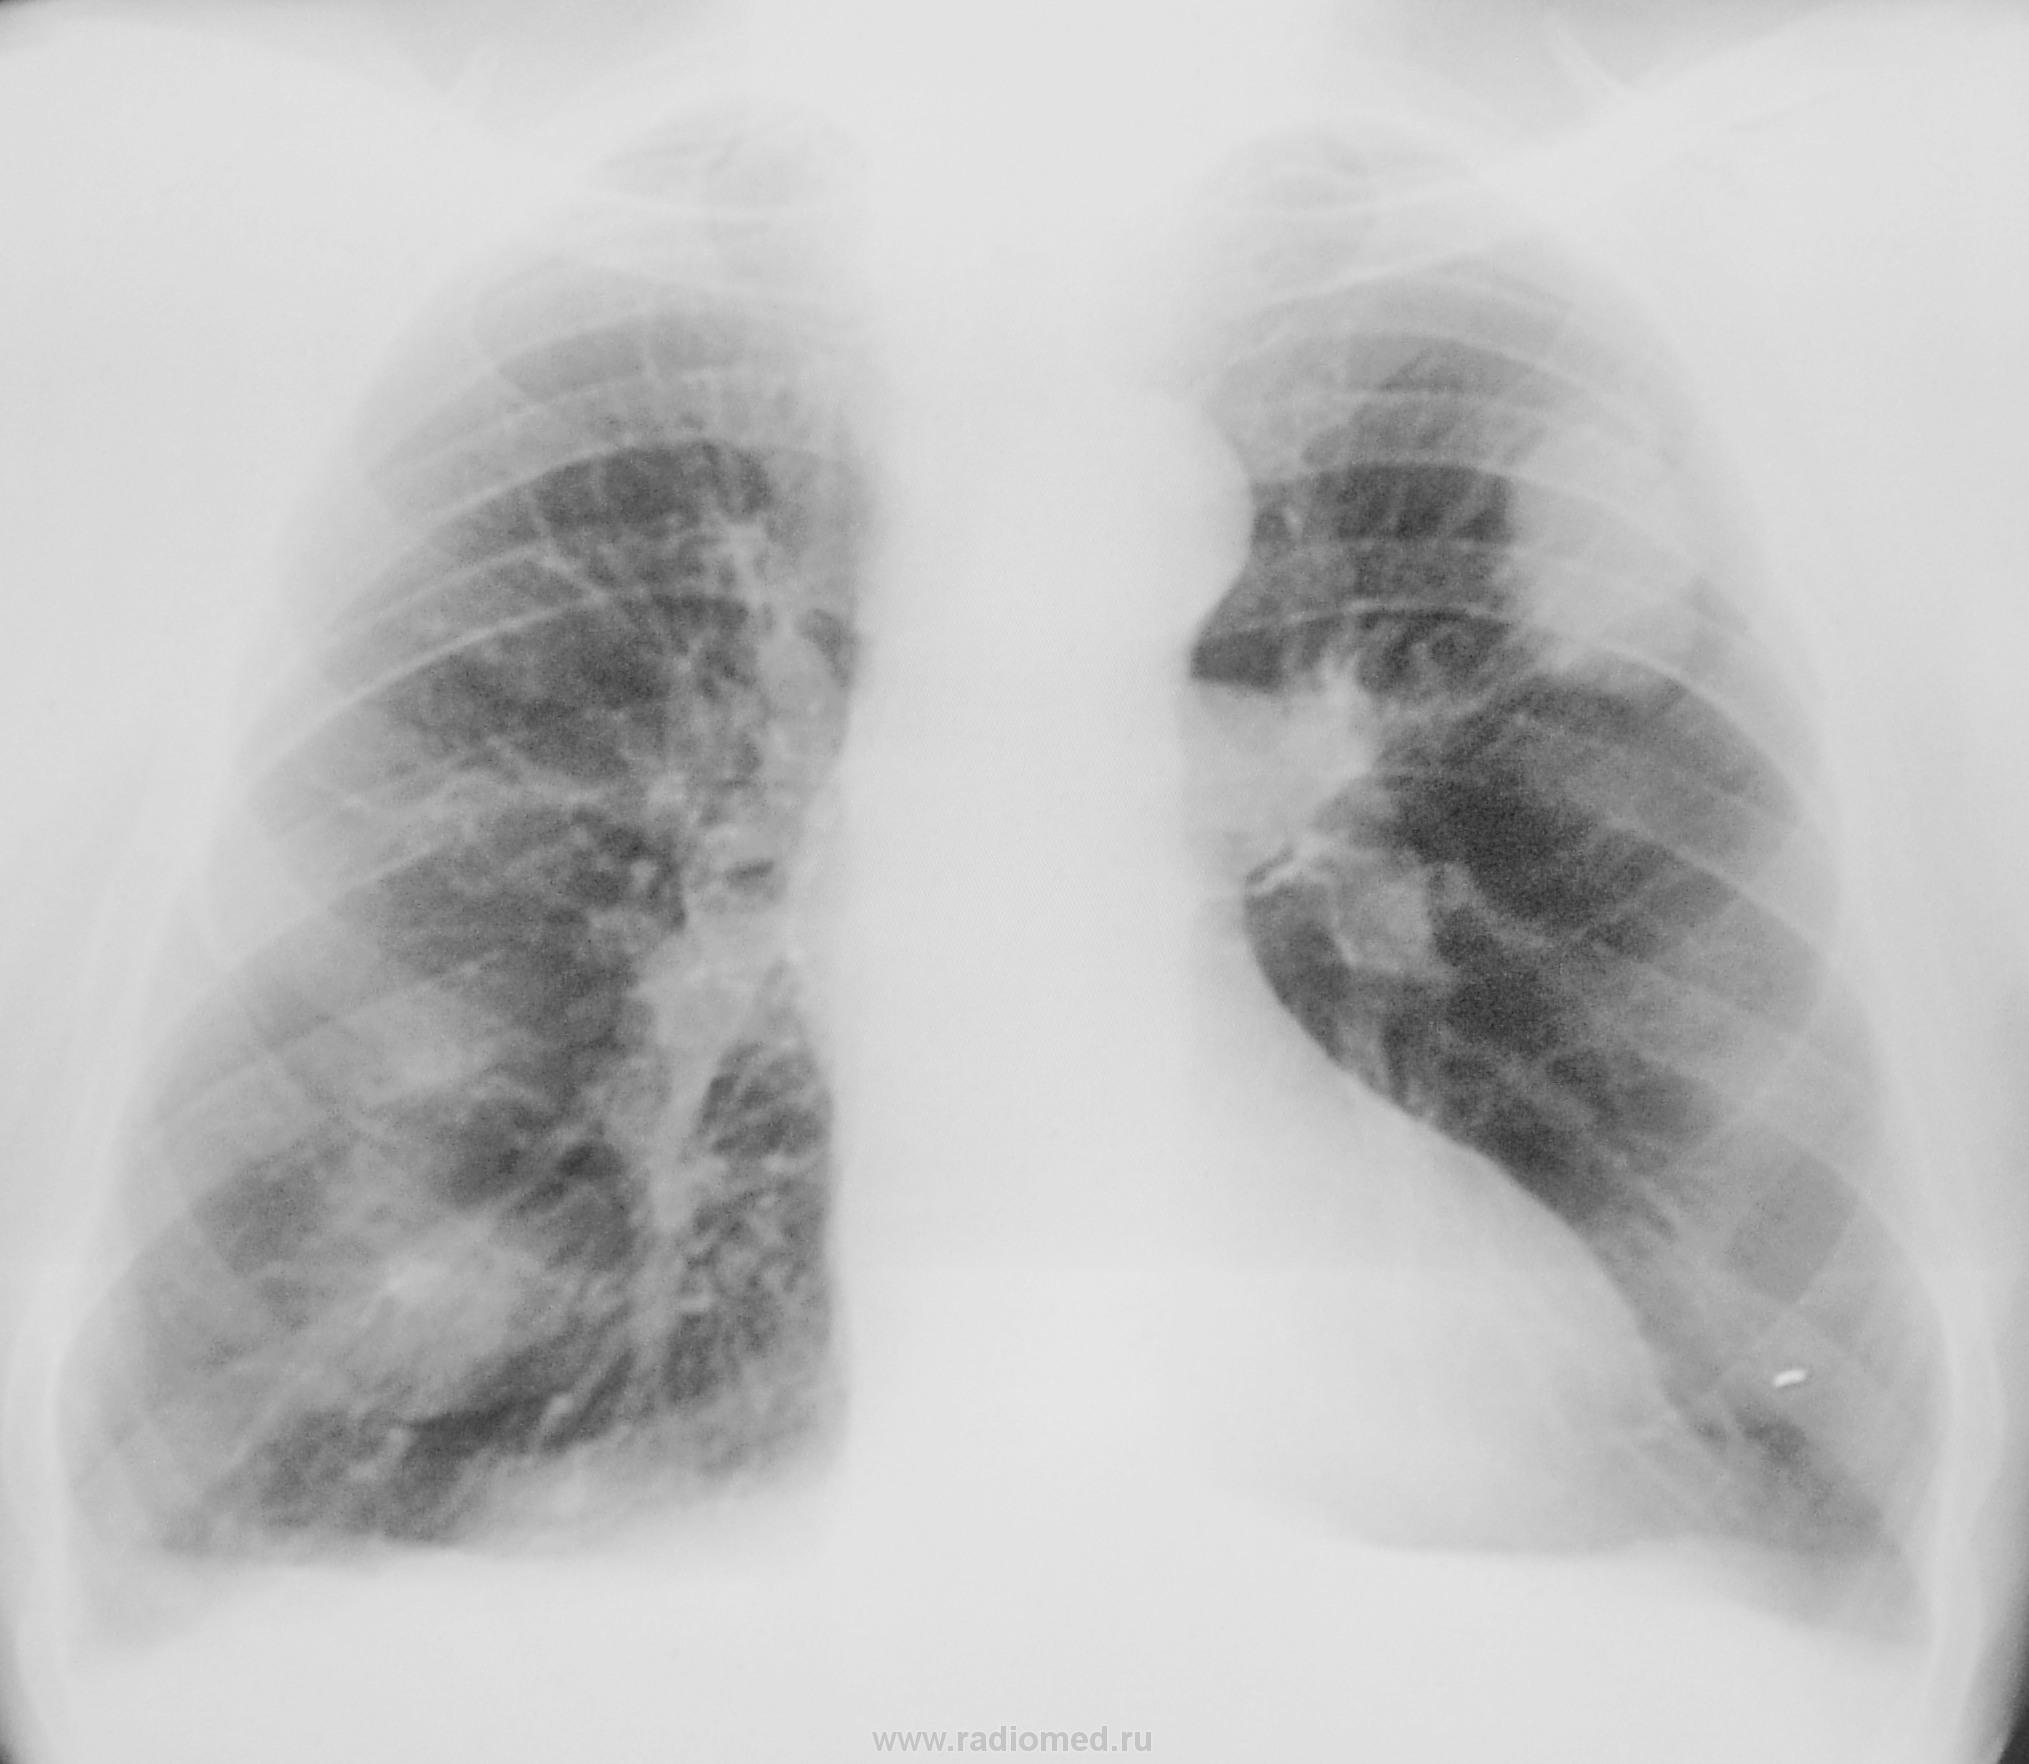

Взяли на контроль после флюорографии, сделали обзорный снимок и задумались, зачем вызвали?

Какие будут мнения уважаемые коллеги?

Нас смутили тенюхи слева на уровне 3 ребра. Посидели с коллегой фтизиатром, но фтизиатрического "возбуждения" не наступило. Был сотворен протокол, указаны те очаги и пациент был отпущен.

Такое впечатление, что то прошлое не имеет никакого отношения к тому, что мы видим сейчас. Даже если очаги были слева, то сейчас и тени другие, и стало их на порядок больше. Слева образование с не ровными бугристыми контурами, очень похоже на периферию, а справа их минимум две. Множественные некрасивые тени-с большей вероятностью МТS. Пациент-мужчина, что с толстой кишкой и предстательной железой?

Наталья Васильевна, так чего же на томограммах и намека нет на проблемы справа? Сдается мне, что то - игра теней. А вот периферический слева - тут не поспоришь. Уж больно он не похож на метастаз...

уж очень оно похоже на периферический рак

морфологическая верификация диагноза. Какие доводы в пользу заполненной ретенционной бронхогенной кисты легкого были у меня? Излагаю. Я предположил кисту при поступлении на сайт рисунка №1. Заметил, что она напоминает "гроздь винограда", что описано было давно в русской литературе. После этого, я вернулся к рисунку №2 и обратил внимание на вытянутую двояковыпуклую форму тени по ходу бронха. Затем ещё раз просмотрел рисунок №3, где отчетливо видно уже две тени, напоминающие растянутые и заполненные мелкие бронхи. После этого внимание привлекли четкие контуры "грозди", неизмененный окружающий фон, однородная структура тени, а также локализация тени в субаксиллярном сегменте. Не увидел я и реакции регионарных лимфатических узлов к корне левого легкого. К рентгеновской картине добавил очень быстрый рост тени и то, что больной выявлен при проверочной флюорографии (значит болезнь протекает бессимптомно). Все эти признаки, вместе взятые, дали мне возможность предположить ретенционную бронхогенную кисту легкого. Не исключаю, что мое заключение не совсем точное. Вы, уважаемый Валентин Львович задали вопрос. Я на него Вам ответил. С уважением Nik.